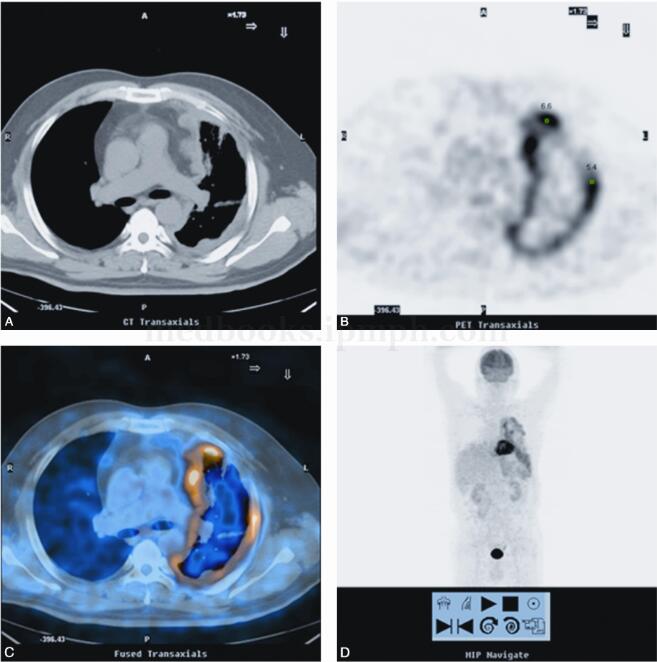

男性,58岁,左侧胸背部疼痛伴麻木3个月(图1、图2)。

图2 A.CT图像示左肺体积减小,左侧胸膜弥漫性不均匀增厚,局部形成软组织结节,左肺见多发索条及斑片影;B.同层PET图像示FDG代谢异常增高(SUVmax=6.9),左肺见多发索条及斑片影,FDG代谢未见增高;C.同层PET/CT融合图像示增厚胸膜FDG代谢不同程度增高;D.PET MIP图